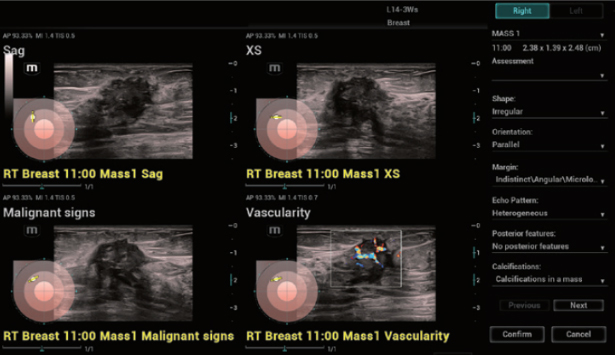

Resona I9 provides comprehensive clinical solutions for dedicated applications. Based on in-depth insights into different clinical scenarios, it delivers innovations that give users extreme clarity, outstanding intelligence and enhanced diagnostic confidence.